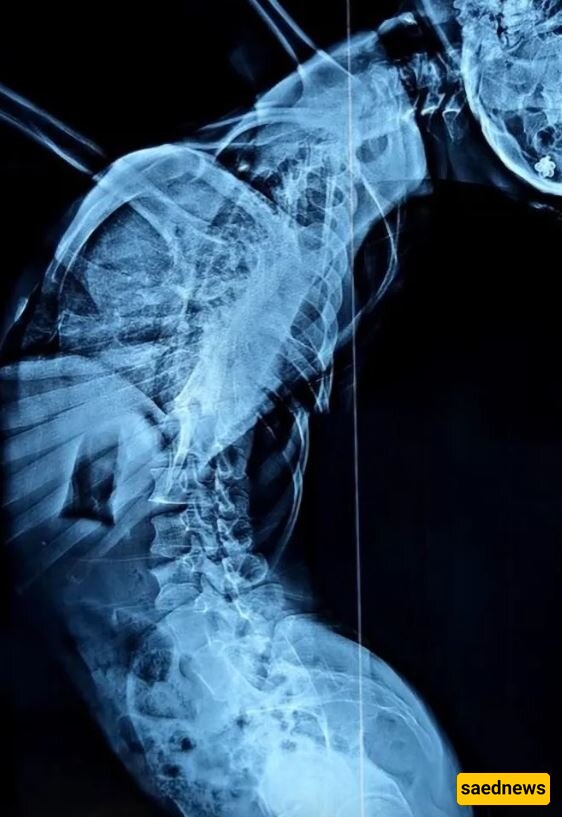

She was diagnosed with scoliosis, a disorder in which the spine twists or curves sideways.

The 37-year-old woman struggled immensely with walking, and her head nearly reached her waist—meaning that when she stood, the unidentified patient from Guizhou Province, China, measured only 1.2 meters tall.

Footage of her shows her Z-shaped body bent 180 degrees backward and to the right. In another video, despite her deteriorating condition, she can be seen trying to take her children to school.